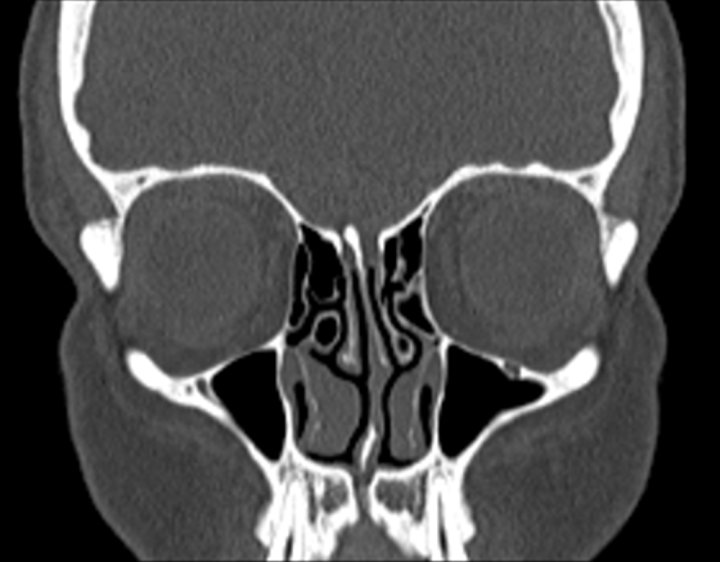

Click any image for labels.